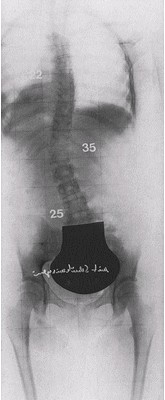

In 1989, 311 scoliosis patients 12 - 69 years old with an average Cobb angle of 50.5 degrees filled out pain questionnaires at the beginning and end of their treatment programs at the Katharina Schroth Klinik. They were asked to rate their pain on a scale of 0 - 5